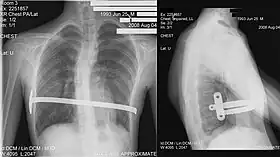

![]() X-Ray of a 15-year-old male after undergoing the procedure | |

Through two small incisions in the side of the chest, an introducer is pushed along posterior to the sternum and ribs, and anterior to the heart and lungs. Then a concave stainless steel bar is slipped under the sternum, through the incisions in the side of the chest. A third, smaller incision is made to insert a thoracoscope (small camera) used to help guide the bar. Taller patients, older patients, or patients requiring extensive correction may receive two or more bars. All bars may be placed through two incisions or additional incisions may be made. The bar is then flipped, and the sternum pops out. To support the bar and keep it in place, a metal plate called a stabilizer may be inserted with the bar on one side of the torso. PDS sutures may also be used in addition to the stabilizer. The stabilizer fits around the bar and into the ribcage. The bar and stabilizer are secured with sutures that dissolve in about six months.

After a period of two to four years,[3]: 343 the surgical stainless steel bar is removed from the patient's chest. This procedure lasts approximately ninety minutes. The length of time that the patient stays at the hospital following the bar removal procedure varies, depending on the amount of new bone growth surrounding the bar. Accordingly, the length of time may range from a few hours to several days, or up to one week.